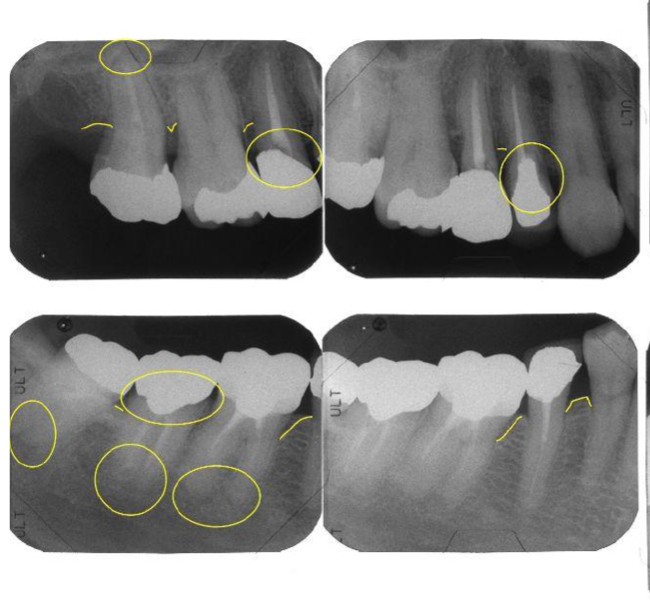

治療前

| 主訴 | 左上のブリッジが欠けた。 金属を白くしたい。歯並びも気になる。 |

| 治療内容 | 全顎治療:歯周病治療、インプラント治療、GBR、根管治療、矯正治療、 ダイレクトボンディング、セラミック治療、親知らずの抜歯 |